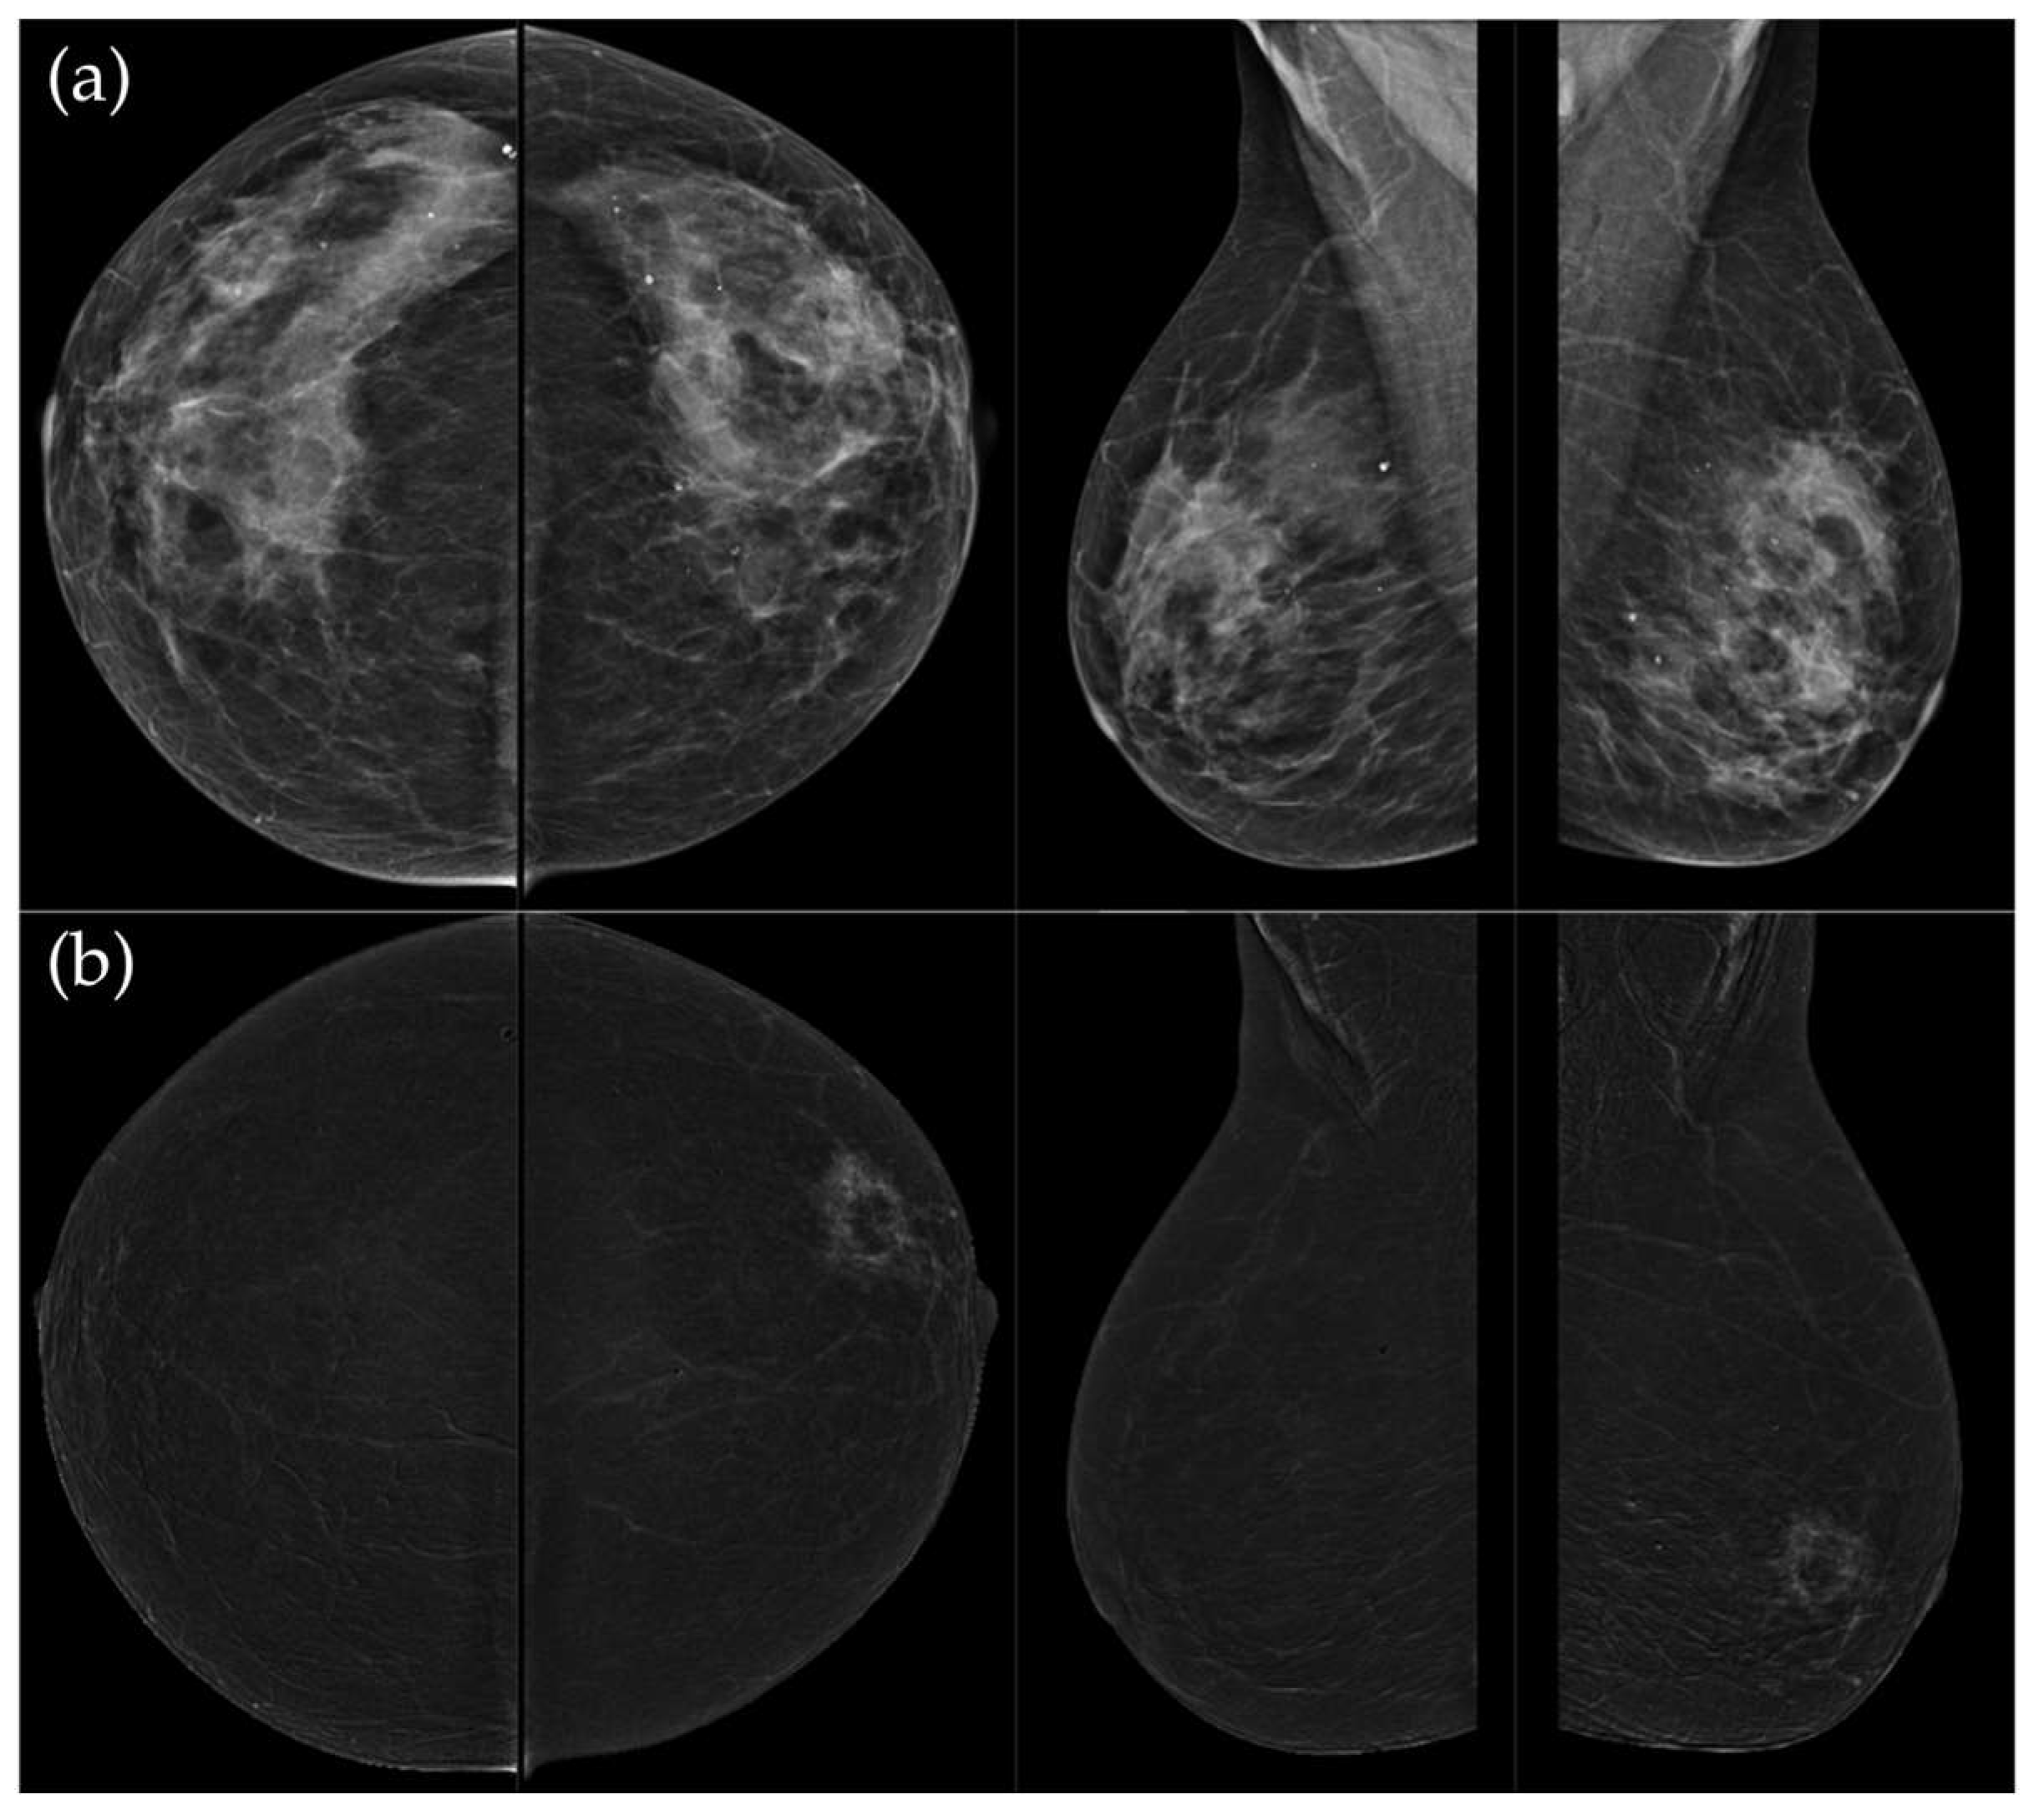

Figure 4. (a) Standard CC and MLO low-energy views reveal an irregular, spiculated mass with associated retraction of Cooper’s ligaments in the upper outer quadrant of the left breast. No suspicious microcalcifications are seen. The right breast appears unremarkable. (b) Recombined contrast-enhanced images (CC and MLO views) demonstrate an irregular, non-circumscribed lesion in the upper outer quadrant of the left breast with rapid early heterogeneous enhancement. Partially visualized axillary conglomerate on the left also demonstrates heterogeneous contrast enhancement in the early phase. Contralateral axilla is unremarkable. Histopathological analysis confirmed a Luminal B breast carcinoma.

Figure 5. (a) Low-energy CC and MLO views reveal a focal asymmetry with associated suspicious microcalcifications and retraction of Cooper’s ligaments in the upper outer quadrant of the left breast. An oval, well-circumscribed mass with circumscribed margins is seen at the junction of the lower quadrants of the right breast. (b) Recombined contrast-enhanced images (CC and MLO views) demonstrate a large inhomogeneous enhancing area, with two closely situated, partially marginated masses in the upper outer quadrant of the left breast. The right breast lesion shows homogeneous early enhancement without washout on delayed images—findings suggestive of a benign lymph node or fibroadenoma. In the visualized portions of both axillae, no pathologically enhancing lymph nodes are identified. Histopathological analysis confirmed a HER2-enriched breast carcinoma.